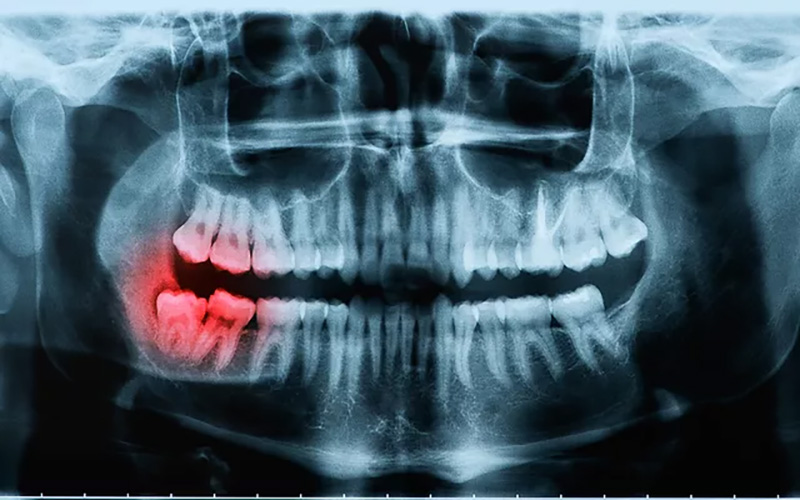

Chụp X quang là một phương pháp chẩn đoán hình ảnh y tế được sử dụng để tạo ra các hình ảnh bên trong cơ thể bằng cách sử dụng tia X. Trong quá trình chụp X quang, tia X được điều chỉnh để đi qua cơ thể tạo ra các hình ảnh chi tiết về hệ cơ xương và một số mô trong cơ thể. Từ đó sẽ giúp cho việc chẩn đoán các bệnh lý liên quan đến xương khớp, tim mạch và hệ hô hấp.

- Các bệnh răng miệng: Sâu răng, răng mọc lệch, viêm nướu,…

- X quang giúp hiển thị rõ ràng tình trạng gãy xương và nhiễm trùng ở xương/răng.

- Chụp X quang có thể giúp chẩn đoán dễ dàng các vấn đề về viêm khớp hoặc những tổn thương khớp.

- X-quang có thể đo mật độ xương cũng như cho kết quả hình ảnh ung thư xương.

- Máy X quang cũng có thể giúp nha sĩ kiểm tra được các lỗ sâu răng.